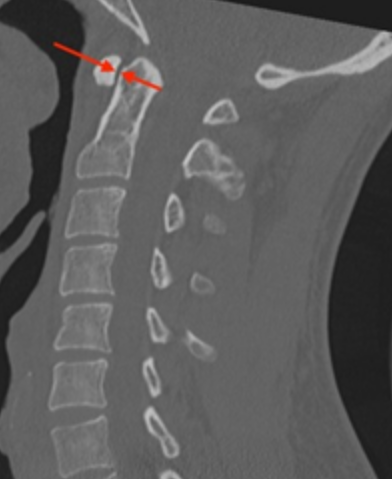

Image Type Cervical Spine X-Ray CT Scan MRI Scan Atlantodental Interval (ADI) Basion–Axial Interval (BAI) Basion–Dens Interval (BDI) Canal Occupying Ratio (COR) Clivo-Axial Angle Facet Joint Overlap (Percent Overlap Method) Facet Joint Step-Off/Dislocation Grabb-Oakes Measurement (pB - C2 line) Occipital Condyle–C1 Interval (CCI) Posterior Atlantodental Interval (PADI) Power’s Ratio Sagittal Vertical Axis (SVA) Segmental Angle Translation on Sagittal Reconstruction